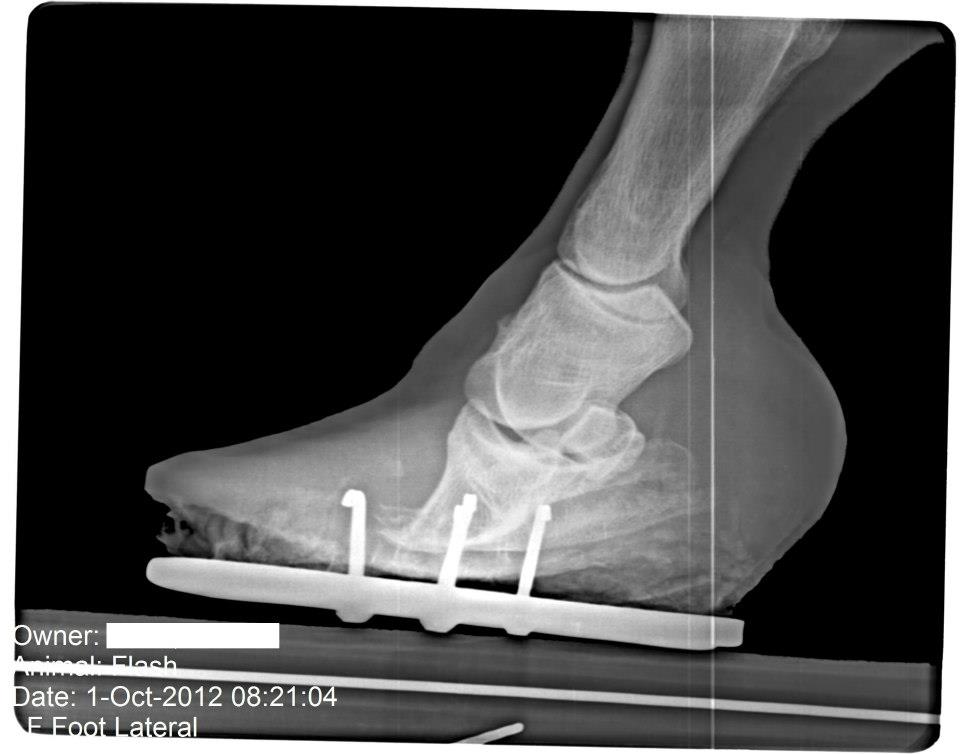

Horse Founder X Rays . founder in horses, also called laminitis, is the profound swelling and pain in the hoof when. radiographic studies are an essential. This can reveal underlying causes like metabolic disorders that can predispose a horse to founder. These can show any rotation or sinking of the coffin bone inside the hoof, providing a clear picture of the severity of the founder.

radiographic studies are an essential. These can show any rotation or sinking of the coffin bone inside the hoof, providing a clear picture of the severity of the founder. founder in horses, also called laminitis, is the profound swelling and pain in the hoof when. This can reveal underlying causes like metabolic disorders that can predispose a horse to founder.

Founder Info for Horse Owners! Leo's Radiographs (aka xrays) Horse Founder X Rays These can show any rotation or sinking of the coffin bone inside the hoof, providing a clear picture of the severity of the founder. founder in horses, also called laminitis, is the profound swelling and pain in the hoof when. This can reveal underlying causes like metabolic disorders that can predispose a horse to founder. radiographic studies are. Horse Founder X Rays.

Founder Info for Horse Owners! Leo's Radiographs (aka xrays) Horse Founder X Rays This can reveal underlying causes like metabolic disorders that can predispose a horse to founder. founder in horses, also called laminitis, is the profound swelling and pain in the hoof when. These can show any rotation or sinking of the coffin bone inside the hoof, providing a clear picture of the severity of the founder. radiographic studies are. Horse Founder X Rays.

Founder Info for Horse Owners! Leo's Radiographs (aka xrays) Horse Founder X Rays radiographic studies are an essential. This can reveal underlying causes like metabolic disorders that can predispose a horse to founder. These can show any rotation or sinking of the coffin bone inside the hoof, providing a clear picture of the severity of the founder. founder in horses, also called laminitis, is the profound swelling and pain in the. Horse Founder X Rays.